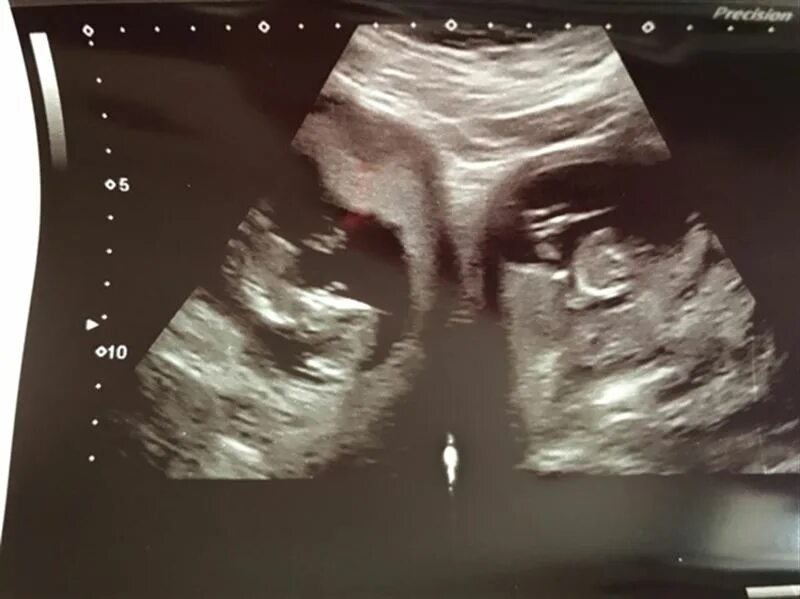

27 недель беременности двойня